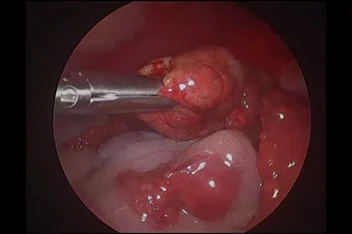

부울경 최초 ‘양방향 척추내시경’ 도입

정밀하고 덜 아픈 척추 수술의 새로운 패러다임

양방향 척추 내시경 BESS, Biportal Endoscopic Spine Surgery

기존의 단일 포털 내시경(uniportal endoscopy)의 한계를 극복한

정밀한 양손 작업이 가능한 최소침습 기술입니다.

리본동물의료센터 2025년 1월부터 부울경 최초로 양방향 척추 내시경을 도입해왔으며, 영남권 최다 임상 CASE를 축적하고 있습니다.

양방형 척추 내시경 수술의 핵심 장점

• 정밀한 수술 조작

• 근육 인대 손상 최소화

• 절개 최소화

• 빠른 회복과 낮은 통증

• 고배율 직시 시야 확보

양방형 척추 내시경 수술 전

양방형 척추 내시경 수술 후